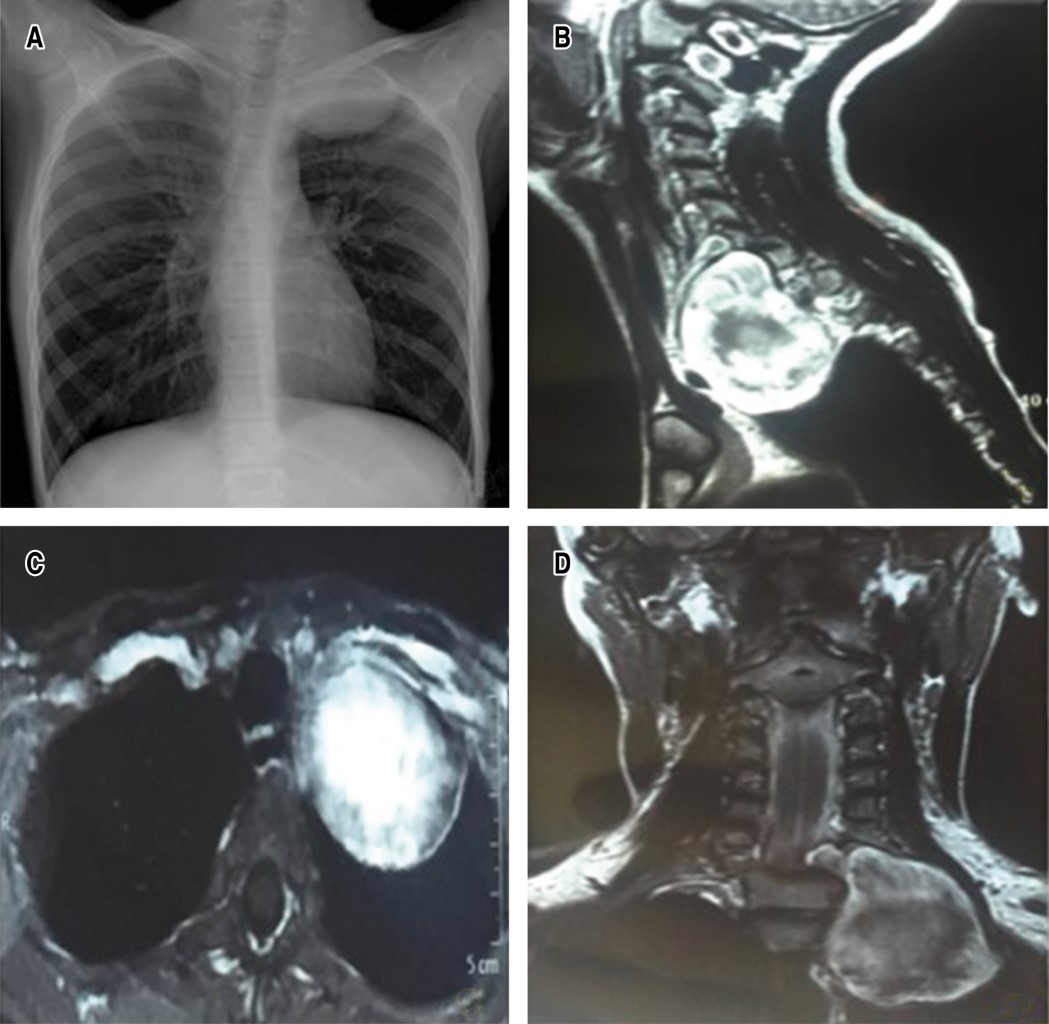

Magnetic resonance imaging shows extradural lesion originating at the level of the left C7-T1 conjunctival foramen, widening and rostral extension towards the neck and displacement of the trachea and esophagus and in contact with the carotid sheath and invasion towards the ipsilateral mediastinal region. Electromyography was performed, showing a decrease in the amplitude of sensory and motor latencies of the left ulnar nerve (Figure 1A-D).

Color Doppler ultrasonography and tomography could show that the nerves enter eccentrically to the schwannoma, which in turn is not observed in neurofibroma (main differential diagnosis and prognosis); however, schwannomas are iso to hypointense in T1 and hyperintense in T2 of gadolinium magnetic resonance imaging, defining the preoperative anatomical relationships as a study protocol of the brachial plexus and thoracic sulcus.5,6 However, the hard and invasive consistency of the lesion associated with systemic symptoms with adenopathies could propose fine needle aspiration biopsy as an alternative to predict a final diagnosis. In our case, the diagnostic association with neurofibromatosis type I was suggestive of brachial plexopathy due to schwannoma.2